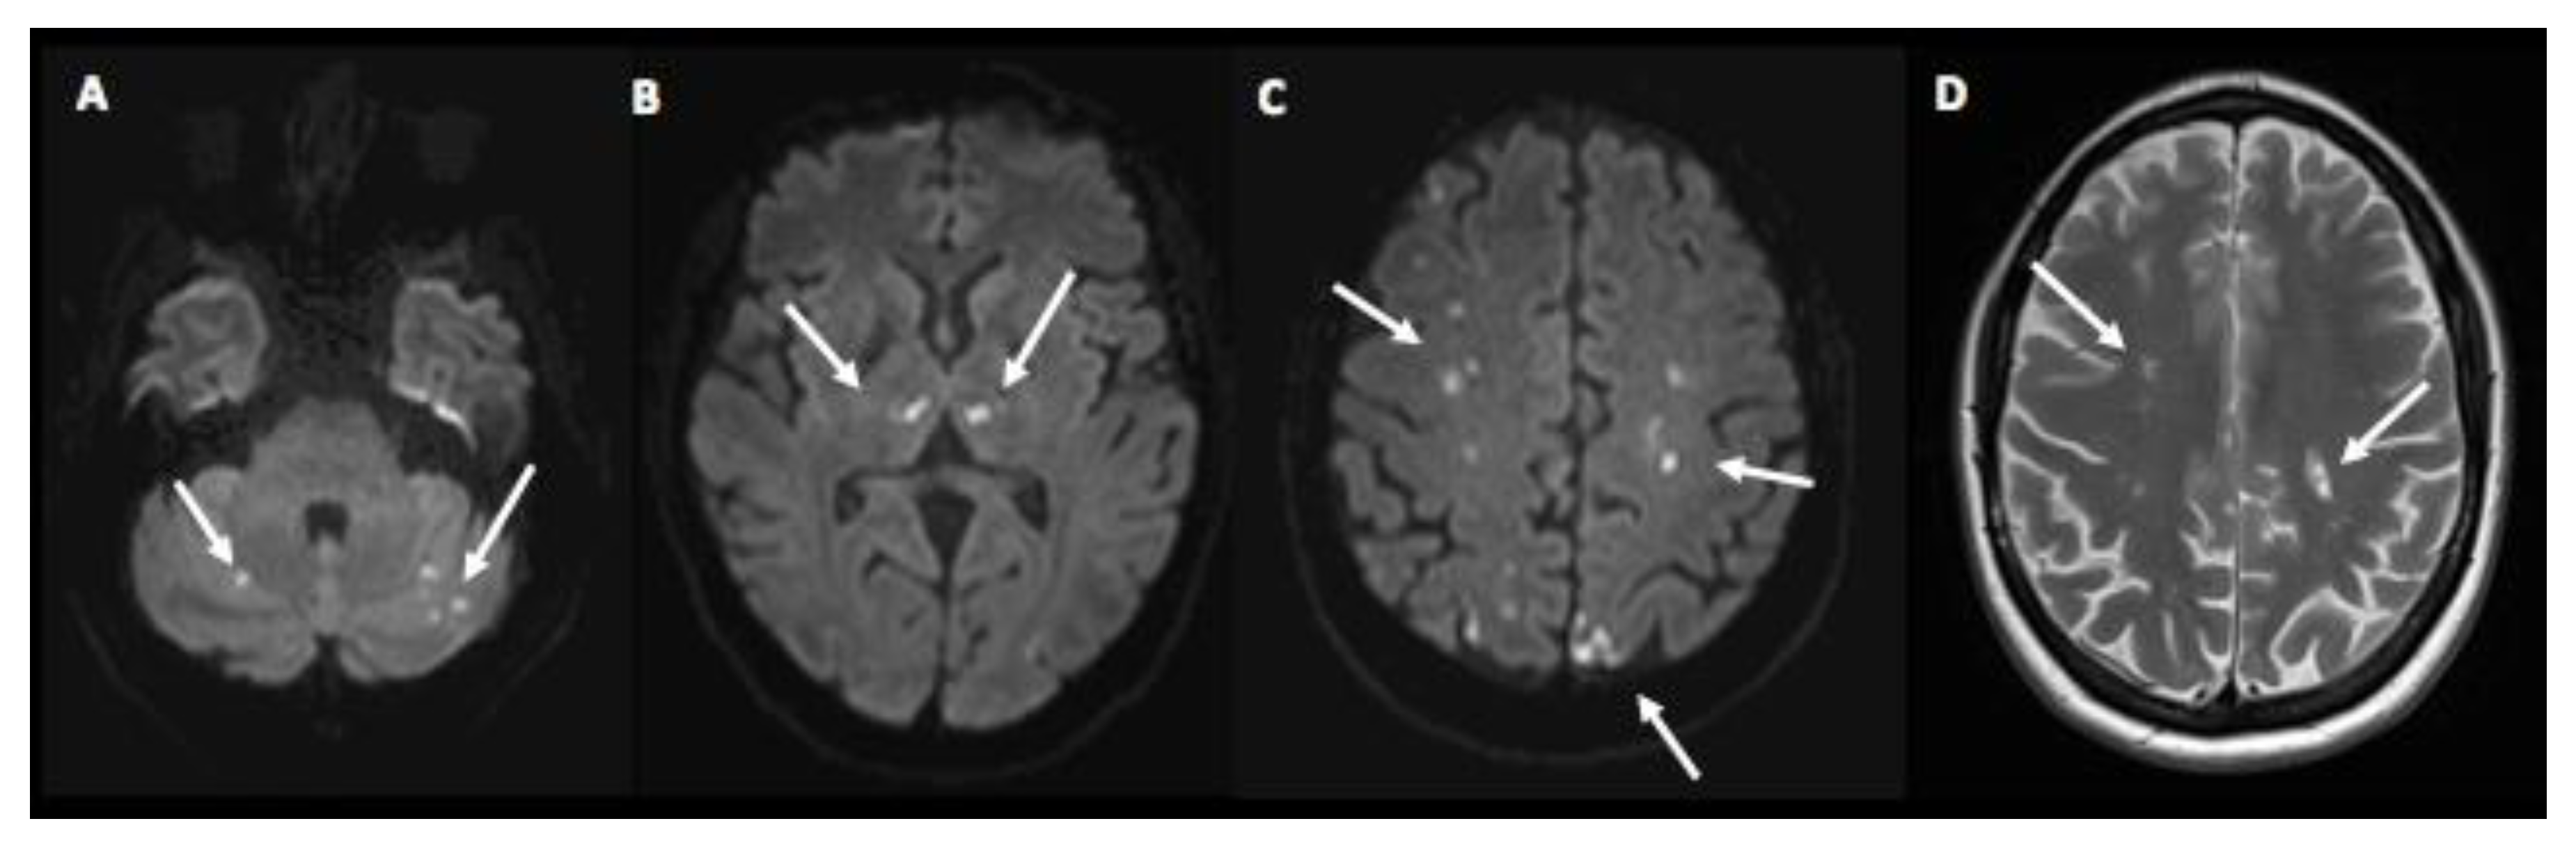

| Present case |

46, F | Allergic rhino-sinusitis and asthma | No | mRNA-1273 | 4 (2nd dose) | Enteritis, fever, fatigue, myalgia | Myocarditis, multiple strokes, immune thrombocytopenia | 8.4 | No | 2 | MP, P, IVIG, RPL, RTX, BEN |